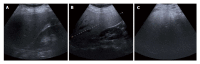

Nonalcoholic fatty liver disease (NAFLD) is one of the most common causes of chronic liver disease and is a major public health problem worldwide. It is a spectrum that includes simple steatosis, nonalcoholic steatohepatitis (NASH), fibrosis and cirrhosis. Recently, NAFLD prevalence in children and adolescents has increased too. The increasing prevalence has resulted in NASH-related chronic liver disease. Therefore, early diagnosis and treatment is quite important. Although liver biopsy is still the gold standard for diagnosis and staging of NAFLD, particularly for the diagnosis of NASH, imaging methods such as ultrasonography, computed tomography, magnetic resonance imaging with chemical shift imaging and especially magnetic resonance spectroscopy and elastography have been increasingly approved as noninvasive alternative methods. The aim of this review is to analyze the diagnostic accuracy and limitations of the imaging methods and recent developments in the diagnosis of NAFLD.